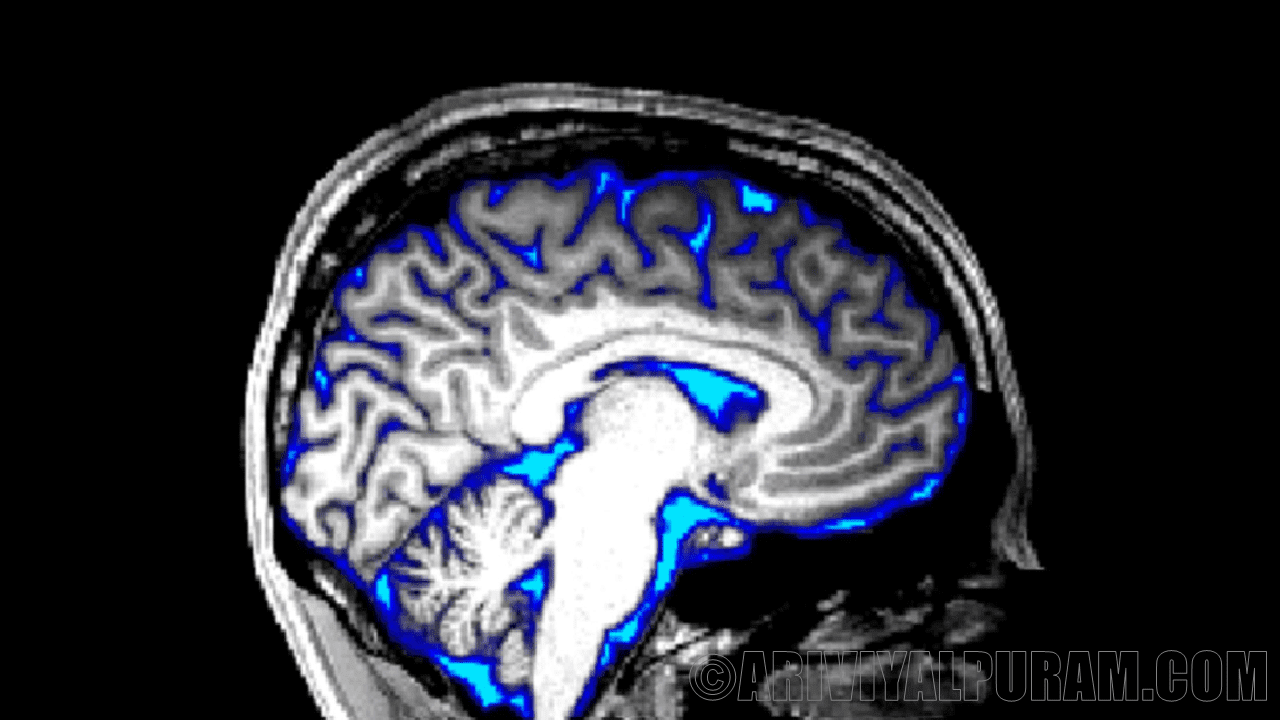

மூளையின் மையத்தில் நான்கு துவாரங்கள் அல்லது வென்ட்ரிக்கிள்கள் உறுப்பைத் தணித்து கழிவுகளை வெளியேற்றும் திரவத்தால் நிறைந்துள்ளன. ஆனால் விண்வெளியில் சிறிய ஈர்ப்பு விசையுடன், விண்வெளி வீரரின் தலையில் திரவங்கள் குவிகின்றன.

எனவே வென்ட்ரிக்கிள்கள் அதிக திரவத்தை எடுத்துக்கொண்டு விரிவடைவதன் மூலம் மாற்றியமைக்கின்றன என்று கெய்னெஸ்வில்லில் உள்ள புளோரிடா பல்கலைக்கழகத்தின் விண்வெளி விஞ்ஞானி ரேச்சல் சீட்லர் கூறுகிறார். விண்வெளி வீரர்கள் பெரும்பாலும் விரிவடைந்த வென்ட்ரிக்கிள்களுடன் பூமிக்குத் திரும்புவதை ஆராய்ச்சியாளர்கள் அறிந்திருந்தனர்.

ஆனால் Seidler மற்றும் சக பணியாளர்கள் விண்வெளியில் செலவழித்த நேரம் அல்லது கடந்த கால விமானங்கள் ஒரு பயணத்தின் போது மூளை எவ்வளவு மாறுகிறது மற்றும் பாதிக்கிறது என்பதைப் பார்க்க விரும்பினர். ஒவ்வொரு விண்வெளி வீரரின் பயணத்திற்கு முன்னும் பின்னும் 30 விண்வெளி வீரர்களின் எம்ஆர்ஐ மூளை ஸ்கேன்களை குழு ஆய்வு செய்தது.

நீண்ட பணி, நான்கு வென்ட்ரிக்கிள்களில் மூன்று அதிகமாக விரிவடைவதாக பகுப்பாய்வு காட்டுகிறது. நான்காவது வென்ட்ரிக்கிள் மிகவும் சிறியது. சாத்தியமான அளவு மாற்றங்கள் கண்டறிய முடியாத அளவுக்கு சிறியதாக இருக்கலாம் என்று சீட்லர் கூறுகிறார். இரண்டு வார பயணங்கள் வென்ட்ரிக்கிள்களில் குறைந்தபட்ச அடையாளத்தை விட்டுச் சென்றாலும், ஆறு மற்றும் 12 மாத பயணங்கள் ஒரு மில்லிலிட்டரின் பின்னங்கள் மூலம் விரிவாக்கத்தை ஏற்படுத்தியது.